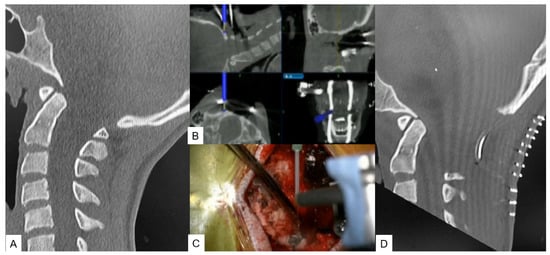

2.2.2. Modified Goel Technique

- Tanaka, M.; Sonawane, S.; Fujiwara, Y.; Uotani, K.; Arataki, S.; Yamauchi, T.; Ye, Y.; Misawa, H. C-arm Free O-arm Navigated Posterior Atlantoaxial Fixation in Down Syndrome: A Technical Note. Acta Med. Okayama 2022, 76, 71–78. [Google Scholar]